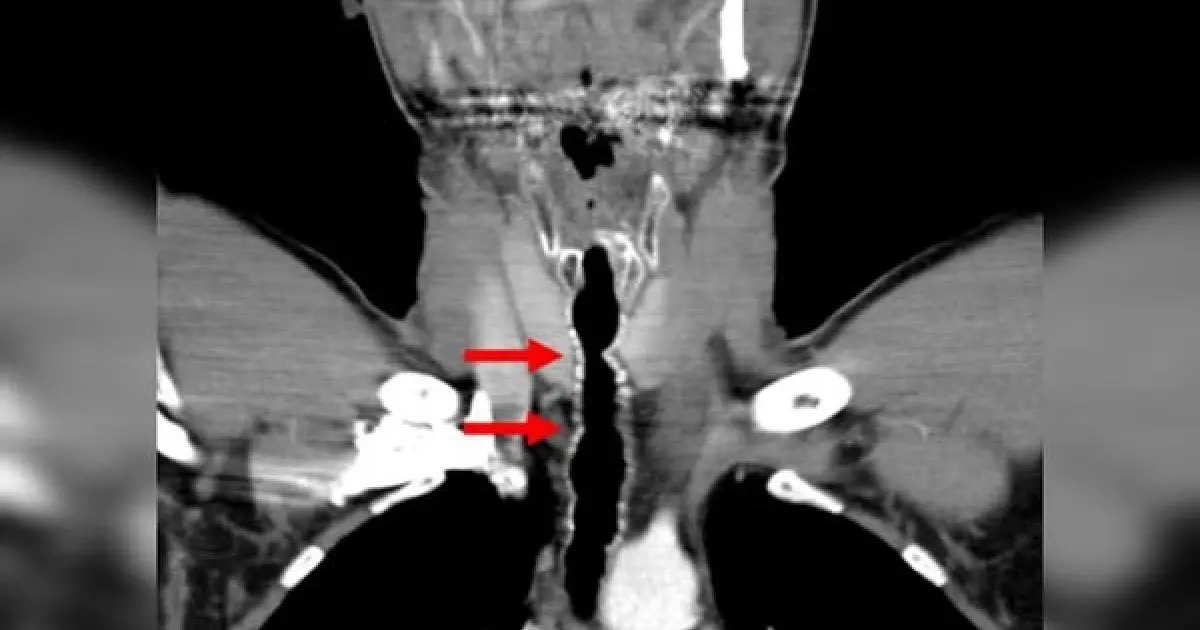

Ao ter 35 anos, os médicos decidiram fazer um exame usando câmeras para entender as origens de tantas complicações e descobriram que ele tinha uma úlcera na traqueia e um conjunto de nove fios de cabelo crescendo perto das pregas vocais.

Mesmo os pêlos tendo sido removidos manualmente com uma “depilação endoscópica por fórceps”, como descrevem os médicos, foram necessárias várias sessões de manutenção anuais para remover repetidamente os fios com comprimento de até 5 cm.